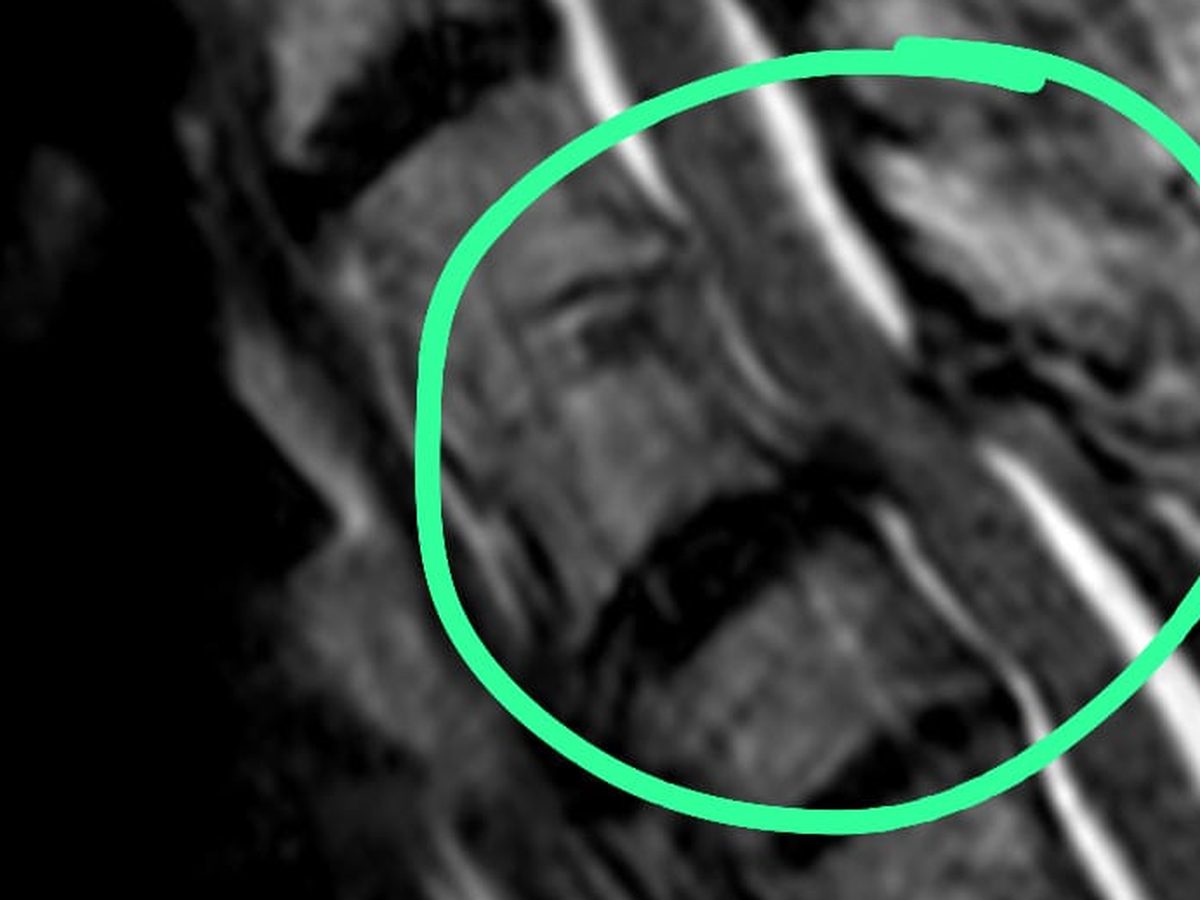

Estabilizada la situación de su sistema digestivo, el personal de la Clínica Unión, acertadamente, determinó que sería prudente hacerle una resonancia magnética para saber a ciencia cierta el efecto de la caída. El resultado: una compresión en su médula espinal (mielopatía cervical más mielomalacia de nivel c-4 y c-5). La noticia fue un baldado de agua fría para toda la familia, pues el personal médico del hospital fue enfático en que de no recibir una cirugía inmediatamente, perdería movilidad de la cintura hacia arriba.